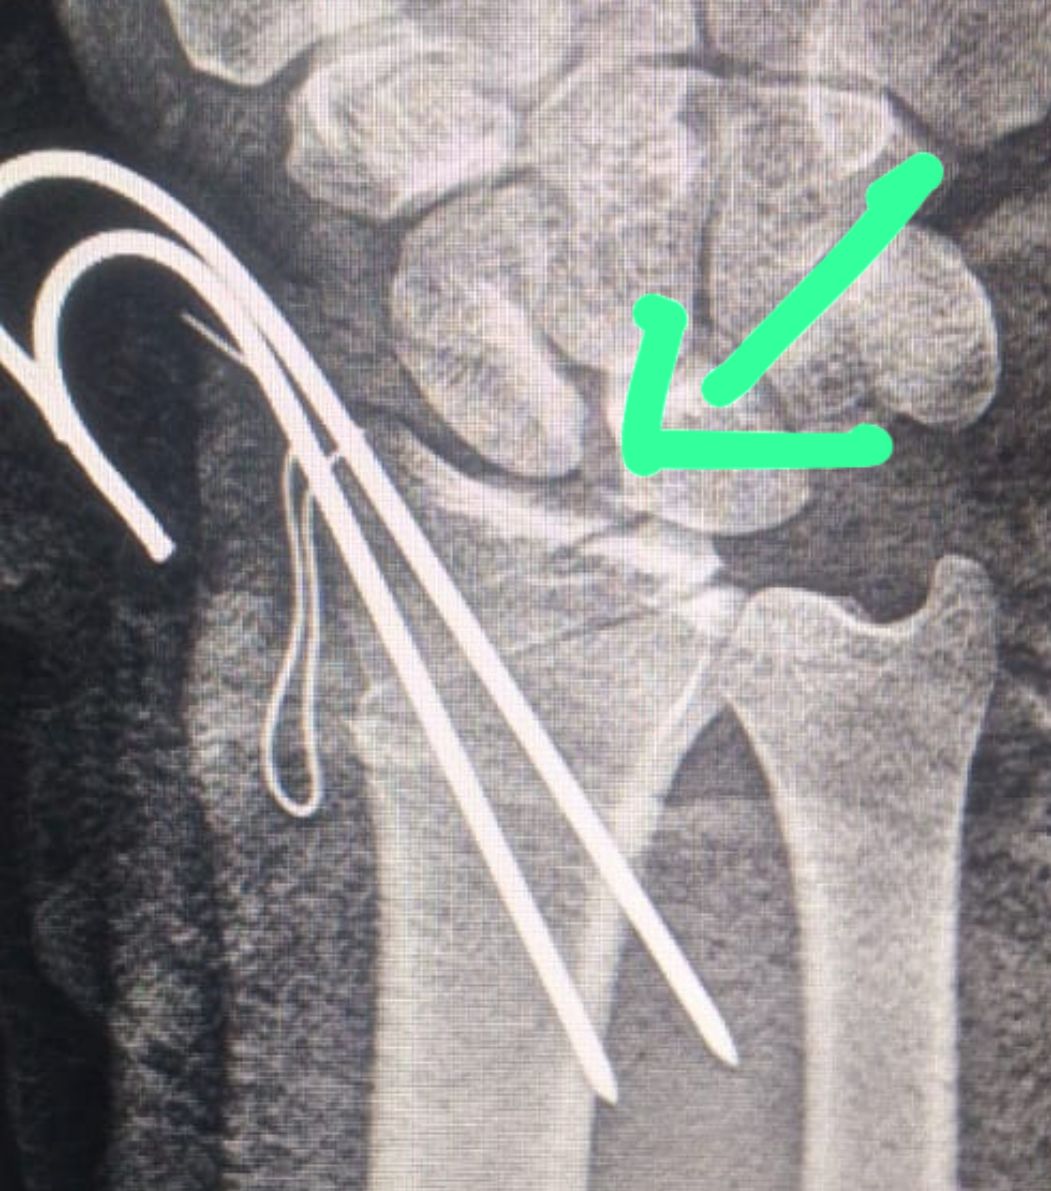

وأضاف مدكور أن حالة المريض كانت حرجة للغاية، إذ وصل إلى قسم الطوارئ وهو يعاني من بتر شبه كامل باليد اليمنى إثر إصابة قطعية عنيفة بآلة حادة، امتدت لتشمل الأوتار، والشرايين، والأعصاب الطرفية، إضافة إلى العظام والمفصل الرسغي، مع نزيف شديد وفقدان شبه تام للحركة والإحساس.

وأوضح الدكتور أحمد البيلي، وكيل المديرية للطب العلاجي، أن الفريق الطبي تعامل بسرعة واحترافية عالية مع الحالة، وتم نقل المريض فورًا إلى غرفة العمليات، حيث جرت الجراحة بدقة متناهية، باستخدام الميكروسكوب الجراحي لإعادة توصيل الأوتار القابضة والباسطة، وربط الشرايين لإعادة التروية الدموية، وإصلاح الأعصاب الطرفية باستخدام خيوط ميكروسكوبية فائقة الدقة.

وأشار البيلي إلى أن المريض خرج من العملية بحالة مستقرة، مع استعادة فورية للتروية الدموية وتحسن تدريجي في الإحساس والحركة، وتم إدخاله في برنامج تأهيلي متكامل بإشراف فريق العلاج الطبيعي بالمستشفى.